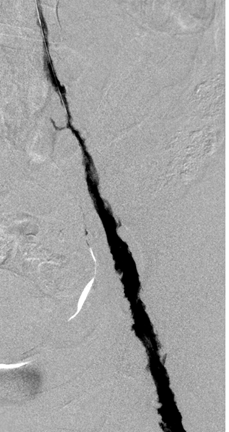

Acceso poplíteo; vista de posición decúbito prono de un trombo oclusivo agudo en la vena poplítea izquierda y en la vena femoral.

Acceso poplíteo; vista de posición decúbito prono de un trombo oclusivo agudo en la vena femoral izquierda y en las venas ilíacas.